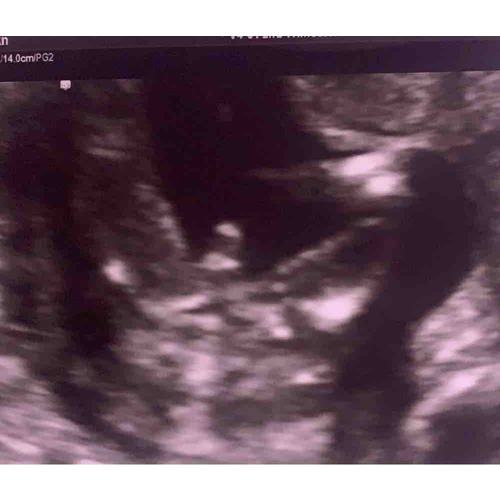

Dit is de echo van onze dochter en jou echo vind ik hier meer op lijken. Deze echo is gemaakt met 14+3 weken